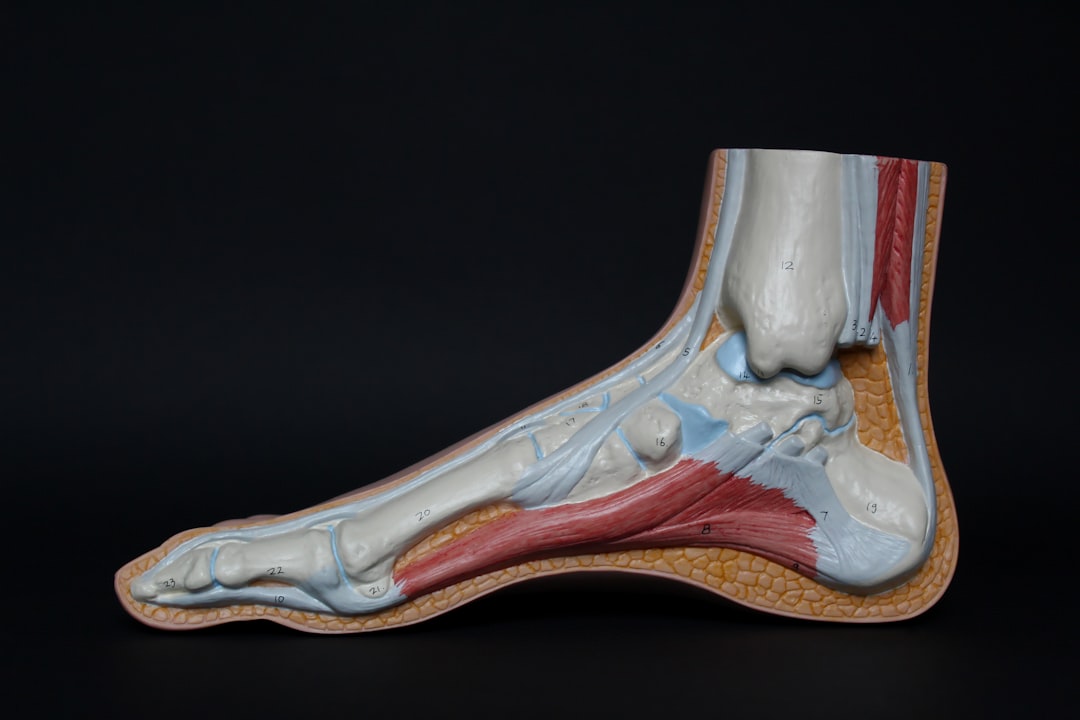

정형외과 중요성

정형외과는 뼈, 관절, 인대 및 근육과 관련된 질환을 치료하는 전문 분야입니다. 모든 연령대에 걸쳐 다양한 문제가 발생할 수 있으며, 이로 인해 일상생활에 큰 불편을 초래할 수 있습니다. 따라서 정형외과 전문의와의 상담은 필수적입니다. 문제를 무시하거나 미루다 보면 상황이 더 심각해질 수 있으니, 적절한 시기에 진료받는 것이 중요합니다. 일요일 정형외과 토요일 진료 시간도 이 점에서 크게 기여할 수 있습니다. 어떤 시간을 선택하든, 전문가의 도움을 받는 것이 성공적인 치료로 가는 첫걸음이죠. 그럼, 이 중요한 진료 시간이 어떻게 운영되는지 살펴볼게요!